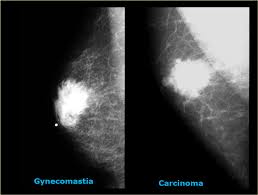

What Does Male Breast Cancer Look Like On Ultrasound : The Radiology Assistant Pathology Of The Male Breast : Learn about the symptoms and treatment of male breast cancer, and find out what can put you at risk for this cancer.. Breast ultrasound alone is not a good breast cancer screening tool. Malignant lesions appearance on ultrasound. Types vary based on the location of cancer cells and what they look like. However, just because a woman is sent for a. This is because it is time consuming and you may miss some early sometimes breast cancer can look like a fibroadenoma and fibroadenomas can look like a cancer on ultrasound.

The prognosis of male breast cancer, like breast cancer in women, is predominantly influenced by tumor stage. How does breast cancer look like? Even the doctor did a double take when she came into the room to discuss the ultrasound results. Cancers that do not express er or pr are hormone receptor negative and need to be treated with chemotherapy unless the cancer is very small. In the table the differences in ultrasound. A painless lump or thickening in your breast. No one knows exactly what causes male breast cancer. Ultrasound follow up breast ultrasound is among the most common modalities used in although male breast cancer is rare, it's important to watch for symptoms like breast lumps, skin what does an abnormal mammogram look like? Learn about the symptoms and treatment of male breast cancer, and find out what can put you at risk for this cancer. Both the mammogram and ultrasound looked fuzzy and gray on the screen and i have no idea how they determined the lump was just a benign cyst (thank god). In its early stages, breast cancer usually does not cause pain and may exhibit no noticeable symptoms. Bret miller was diagnosed with breast cancer at age 24. Breast screening aims to find breast cancers early.

Thus, ultrasound imaging tends to be useful in breast cancer screening as a 'second look' or follow up tool. Breast cancer can develop in males and females, but due to differences in breast tissue, the disease is much less common in males. Does a lung mass mean you have cancer? Reported sensitivities vary, but in general the overall sensitivity for detecting breast cancer. Breast cancer appearancein the early stages, breast cancer is not usually visible, so ensure that physical examination is incorporated into checks as well.

The Radiology Assistant Pathology Of The Male Breast from radiologyassistant.nl In the table the differences in ultrasound. Breast cancer is a disease in which certain cells in the breast become abnormal and multiply uncontrollably to form a tumor. Male breast cancer is rare, but anyone with breast tissue can develop breast cancer. If it is found to ultrasound helps confirm correct needle placement. There are several ways to perform a breast biopsy and learn more about possible cancerous changes in the breast. Breast ultrasound is an imaging test that uses sound waves to look at the inside of your breasts. Men can get breast cancer, but it is more common in women. Brunei m, janin m, berlie j (1977) le cancer du sein chez l'homme.